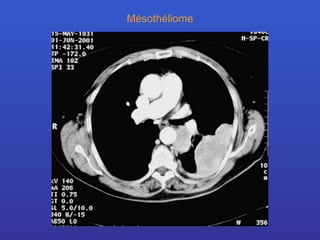

Mésothéliome